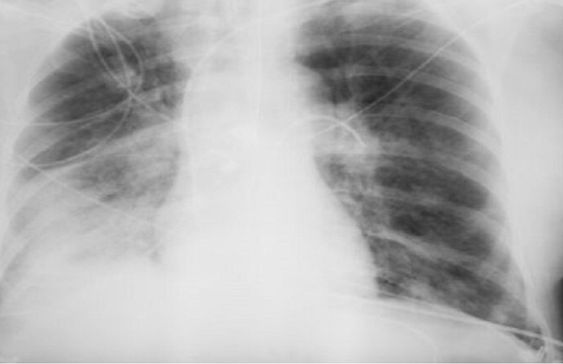

ووفقًا لها، يستخدم الإشعاع فقط في أنواع معينة من الفحوصات، ولا تتضمن جميع طرق التشخيص التعرض للإشعاع. فمثلاً، يستخدم التصوير بالموجات فوق الصوتية والتصوير بالرنين المغناطيسي، وهذه طرق آمنة تمامًا حتى للنساء الحوامل. أما الأشعة السينية فتستخدم فقط في التصوير الشعاعي، والتصوير الفلوري، والتصوير المقطعي المحوسب، بينما لا تتضمن طرق أخرى التعرض للإشعاع.

وتقول: "الأشعة السينية هي إشعاع كهرومغناطيسي، مثل الأشعة فوق البنفسجية والضوء والحرارة. صحيح قد تلحق جرعاتها العالية الضرر بالخلايا، كالذي تسببه حروق الشمس. وأن الاستلقاء تحت أشعة الشمس على الشاطئ دون حماية أخطر بكثير من تصوير بالأشعة السينية للصدر مرة واحدة سنويًا".

وتؤكد بلاتونوفا أن عدم اكتشاف المرض أخطر بكثير من الخضوع للأشعة السينية، حيث تقلل المعدات الحديثة من المخاطر، كما أن الفحوصات في الوقت المناسب تسمح بالكشف السريع عن الأمراض وبدء العلاج.